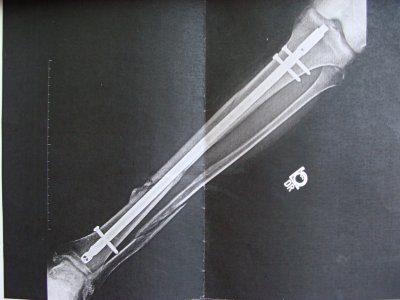

Меня отправили в госпиталь, там сразу же в этот день через пару часов назначили операцию. В ходе операции мне вв большую берцовую кость вставили титановую спицу, которую закрепили двумя шурупами сверху и одним снизу. Малую берцовую кость "собрали в кучу". Извините, не владею медицинской терминологией. Вобщем вот и результат операции

DSC01525.JPG